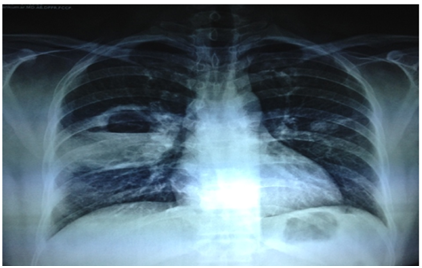

With the use of RC Cornet (Figure 1) along with conventional chest physiotherapy the patient improved better when compared to the day of admission and it was evident subjectively. The quantity of the sputum was reduced since the weight of the sputum mug was 0.5 g and her respiratory rate was 16 breaths per minute post treatment. The perception of dyspnea was reduced due to improvement in gaseous exchange since the secretions block the air passages. After the treatment, the rate of perceived exertion according to Borg scale was 9. On auscultation there were no crepitations and air entry was equal. The percentage of saturation of oxygen was 100% room air. There was also good improvement in radiological findings before and after the treatment and it was shown in (Figures 2 & 3) respectively. When we compared the X-ray findings during the time of admission and 10 days after the treatment, consolidation was markedly reduced and the patient responded well for the treatment.

Figure 3 Chest X –ray Post treatment.